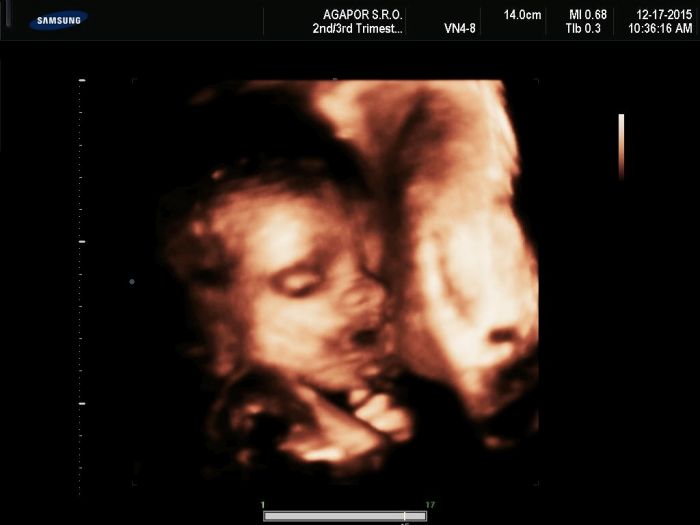

Dekuji,mimco ma 2kg a 200g,měří 42 cm,oproti vašim bříškem je moje obrovské,ze 45 kg jsem nabrala na 66 kg,je to čím dal hur,ale da se to,boli me cela zada,a zebirka,postýlku pro malou uz mam :),kočárek ma prijit zitra,pritel se chce nechat překvapit tak nevi co to je :D,ale moc si pral holcicku,jak je videt na fotce ma po nem cely nos :D,moje mamka trvá na to ze je to kluk :D ale asi ma smulu :D,z mamky strany se rodí samy holky,dukaz toho je ze mam 4 sestry :D,a mamka ma taky jen sestry,z pritele rodiny saméj chlap,tak tchyně ma radost ze konečně holčička :D,neustále kupuje oblečeni pro malou,hlavne ze my nemáme utracet :D ale chapu ji,je to jeji prvni vnouče,chodím na procházky a na výlety porad,i po kopcích :D,k nam domu musim přelest obrovskej kopec po prestavkach,ale da se :),jinak v tehotenstvi me nic nijak netrápí,ne zvracim,nic,jen minuly tyden me pálila žáha,ale to je z jídla,tak jsem omezila moc mastné :),taky jen záda me trapi a koho ne? Je to nezvyk s vahou a stále neumím udržet váhu,uz ani ohnout se :D,ale těšíme se na malou,mate oproti me mala bříška :)